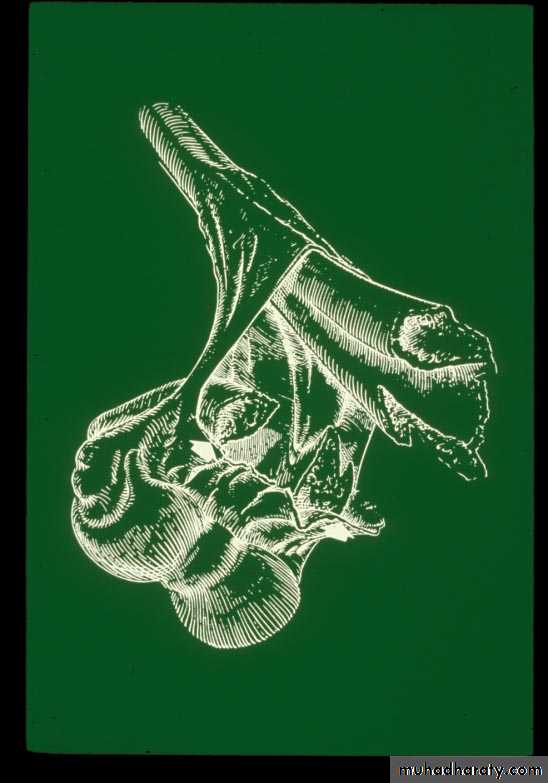

II. Mechanism of Injury

What is the mechanism of injury

for extension type supracondylar fractures ?As the

extended extremityattempts to break

the fall,

the olecranon

is forced

deep into its fossa.

This causes

the humerus to failin the weak metaphyseal

supracondylar area.